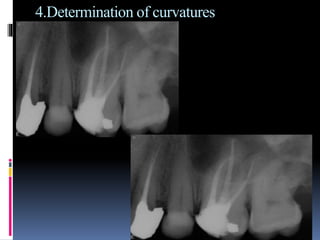

4.Determination of curvatures